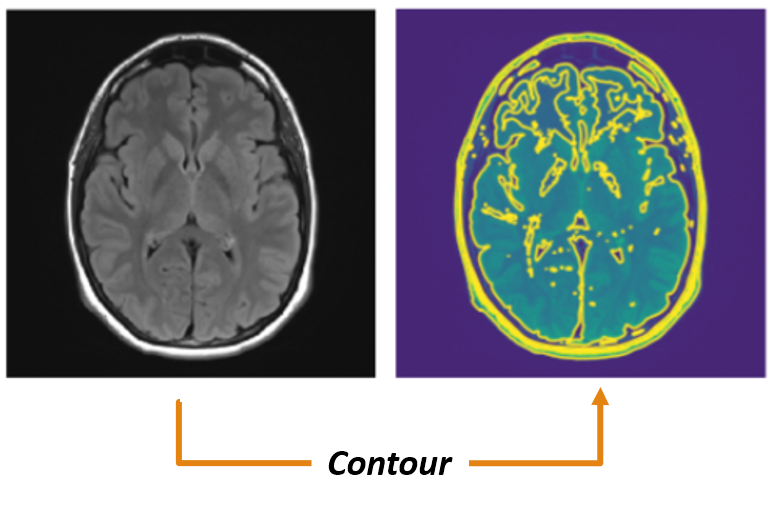

Contour calibration: Regarding MRI images, it is desired to have a higher contrast in the area of interest and lower on the rest. The images that are analyzed till now are in gray scale, hence the different variations in textures are not visible. To know the depth or height of a 3D plane contour lines can be used. It is a function of two variables in a curve along which the function has a constant value so that the curve joins points of equal value. A gray-scale image can also be seen as a 3D representation of the values ranging from 0 to 255 for each pixel of which contour can be plottedkim2014relationship . In this experiment, the MRI has a size of 150 ×\times150 and the contour line can be used to define various colors to the images with varying gray scale. An example showing the contour plot for an MRI sample is shown in Fig. 6(a).

Refer to caption

(a) Contour plot for gray scale MRI image.

Figure 6: An example of special preprocessing technique.